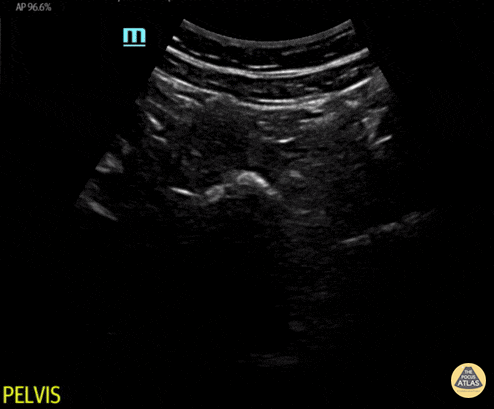

Normal transverse pelvis view. Contributor: Maher M. Abulfaraj, MD, @mahermabulfaraj

View: Unspecified Parasternal Long Axis Parasternal Short Axis Apical Four-Chamber Subcostal Four-Chamber Subcostal Inferior Vena Cava Right Upper Quadrant Left Upper Quadrant Suprapubic Longitudinal Suprapubic Transverse Subxiphoid Anterior Thoracic Phrenic